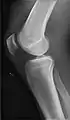

- Knee - AP and Lateral. Intra Condular projections on request

- Patella - Skyline projection

Right knee, anteroposterior

Right knee, lateral

Patella, (slightly skew) skyline